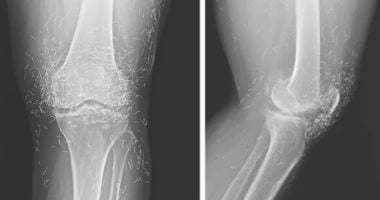

الأطباء الذين أجروا الفحوص لاحظوا في الأشعة السينية مئات النقاط الصغيرة اللامعة حول مفصل الركبة، والتي تبين لاحقا أنها بقايا خيوط ذهبية.كما أظهرت الصور زيادة في سماكة العظام ونمو نتوءات عظمية بجانب المفصل، وهي علامات تقدم التهاب المفاصل.

الأطباء يشيرون أيضا إلى أن وجود هذه الخيوط قد يعيق التشخيص الدقيق، إذ تسبب ظلالا على صور الأشعة السينية، فضلا عن أنها قد تمثل خطرا عند الحاجة إلى الخضوع لتصوير بالرنين المغناطيسي، بسبب احتمالية التفاعل مع المجالات المغناطيسية القوية وما قد يترتب عليه من مخاطر صحية.